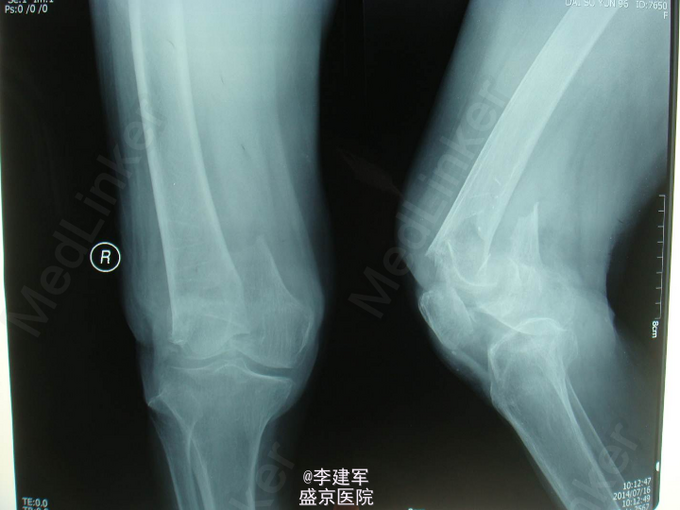

患者性别:女。年龄:94岁 主诉:摔倒后右大腿疼痛肿胀活动受限7小时 患者及其家属自述患者 弯腰拾衣物,起立时一过性意识不清,摔倒,摔倒后意识清楚,右大腿部疼痛肿胀,活动受限,被家属急送往我医院,经检查诊断为"右股骨髁上骨折",收入我科,患者伤来无头痛及发热,无咳嗽咳痰,无腹痛及恶心呕吐,饮食睡眠可,二便正常。

专科查体:右股骨石膏固定中,肿胀,压痛(+), 活动受限,骨擦感及异常活动存在,右下肢无明显麻木,右足趾可活动,足背动脉可触及。 完善心电图,肺部CT,生化检查等,查无手术禁忌症。择期手术治疗

右股骨髁上粉碎性骨折 患者高龄,完善心电图,肺部CT,生化检查等,查无手术禁忌症。择期手术治疗。 手术拟行右股骨髁上粉碎性骨折闭合复位内固定术。 决定使用Liss钢板